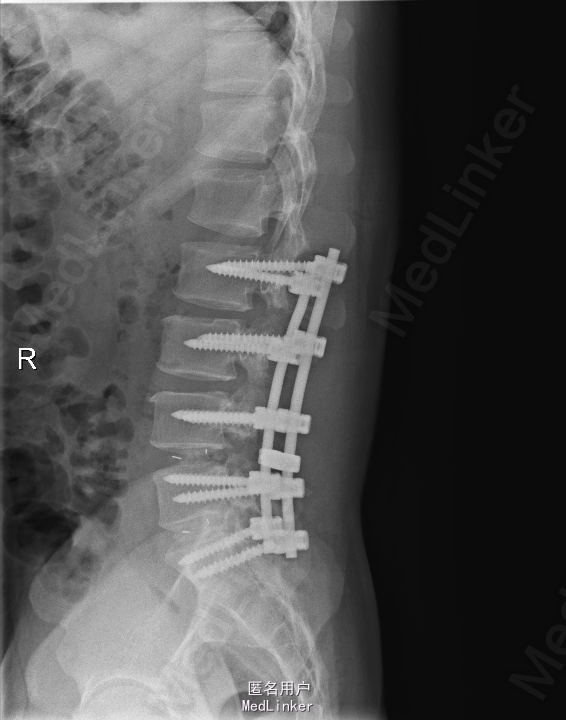

诊断:腰椎间盘突出症并椎管狭窄 处理: 1、完善相关辅助检查,明确诊断,有无手术指证; 2、完善手术评估,有无手术禁忌,手术风险及并发症; 3、在全麻下行腰椎后路多节段减压椎间植骨融合内固定术 4、腰2-3,腰3-4行开窗减压,腰4-5,腰5-骶1行椎间Cage植骨融合

随访: 1、应常规术后1个月、3个月、半年随访; 2、术后患者腰痛较前减轻,下肢麻木感觉较前好转,下肢活动较前有力,屈髋、伸膝、踝背伸肌肌力左侧4级,右侧4-5级,踇背伸、跖屈肌力左侧4级+,右侧4-5级,左侧肢体抬高试验阴性。 讨论: 1、多节段腰椎间盘突出,手术指证把握 2、责任节段的确立,以影像学间盘突出节段为依据,以影像学与临床表现确立责任节段间盘为依据,还是术中探查为金标准? 3、多节段间盘突出,开窗髓核VS椎间植骨融合? 4、开窗髓核与椎间植骨融合相结合,如何确定融合节段与开窗节段? 5、多节段内固定,腰椎活动度影响,稳定与腰椎活动功能的平衡?